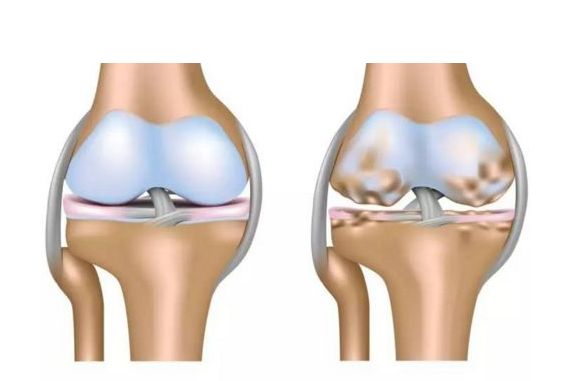

关节炎是怎么形成的?

过了20岁开始,关节就开始退化。

胶原纤维开始交联失去弹性,软骨细胞合成蛋白多糖的能力也下降,造成软骨的弹性下降。

就像塑料衣架在太阳下久晒一样,会变脆,经过一段时间会彻底不能用,骨质疏松的出现,加上运动或外伤原因造成的磨损,关节炎便逐渐形成。